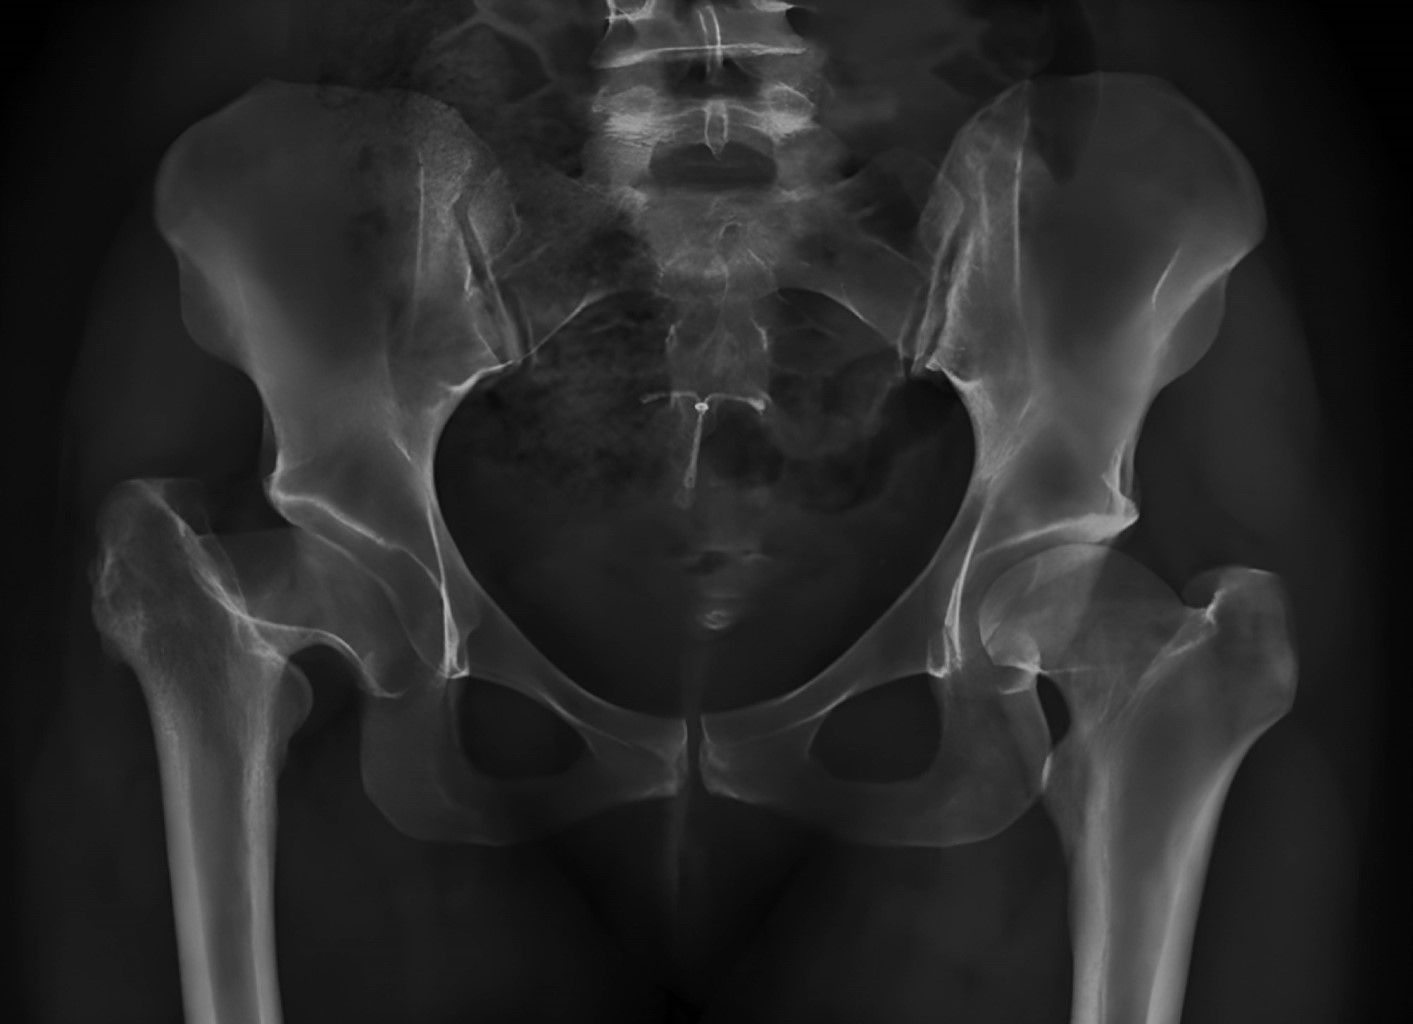

Las secuencias están ilustradas en las Figuras 1, 2, 3, 4, 5, 6 y 7.

EVALUACIÓN RADIOGRÁFICA

La anteversión acetabular tuvo un promedio de 10° (IQR 0°-15°), no observándose componentes acetabulares retroversos. El ángulo de inclinación tuvo una mediana de 43° (rango intercuartílico [RIC]: 38° a 51°). En dos (9.9%) pacientes se detectaron líneas radiolúcidas sin progresión o significancia clínica; el resto de los sujetos presentaron cinco de los signos radiográficos de Moore para osteointegración del cotilo. En 20 pacientes (90.1% de la serie), la medición postoperatoria de la longitud de los miembros no encontró discrepancia entre el operado y el contralateral, en un caso se presentó una hipermetría menor a 0.5 cm y una hipermetría entre 0.5 a 1 cm. En ningún caso hubo disconformidad con el resultado funcional. Se detectó la aparición de calcificaciones heterotópicas de tipo 1 (clasificación de Brooker) en dos casos, sin ninguna relevancia clínica.

Figura 3

Figura 4